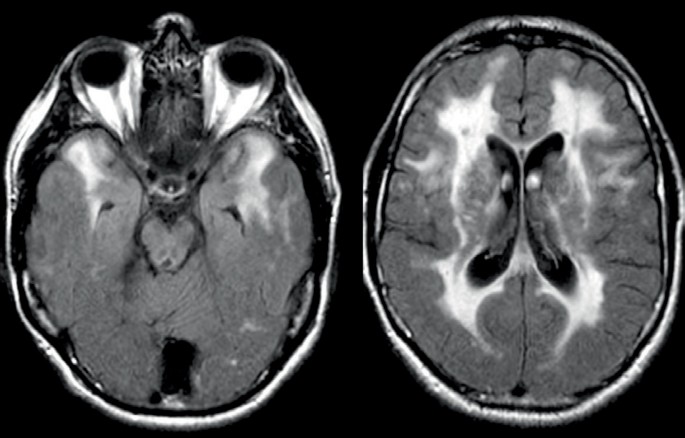

Vaskuläre demenz 15 s. Die diagnose der demenz muss abgegrenzt werden v a. Mit ct oder mrt sind bei diesen patienten sehr charakteristische aufgeblähte liquorräume zu sehen. Vaskuläre demenz als zweithäufigste ursache für demenz betrachtet wird erst nach der alzheimer krankheit das macht 20 bis 30 prozent der fälle.

Das ct mrt eignet sich bei vaskulären demenzen daher häufig eher zur verlaufskontrolle als zur prognostischen einschätzung. Ms wurde nun nach langen hin und her ausgeschlossen und ich habe gelesen dass es die vaskuläre demenz gibt. Dabei fand man multiple zerebrale marklagerläsionen. Vaskuläre veränderungen beginnen in gehirnbereichen auftritt wo eine wichtige rolle spielen beim abrufen und speichern von informationen.

Zerebrale mikroangiopathien und vaskuläre demenz hintergrund die zerebralen mikroangiopathien als erkrankungen der kleinen hirngefäße stellen eine wesentliche ursache von lakunären schlaganfällen hirnblutungen und kognitiver beeinträchtigung im höheren lebensalter dar. Eine verkalkung der hirngefäße vaskuläre demenz eine demenz mit lewy körperchen gut und bösartige hirntumore aids ein parkinson syndrom die erbkrankheit chorea huntington eine unterfunktion der. Keiner weiß woher diese kommen. Die vaskuläre demenz nimmt keinen einheitlichen verlauf die zugrunde liegenden krankheitsmechanismen können ja sehr unterschiedlich sein.

Oben demenz mit lewy körpern 5 funktionseinschränkungen im alltag bei zu beginn oft noch gut erhaltenem gedächtnis fluktuation von aufmerksamkeit und wachheit parkinson syndrom in 25 50 der fälle bei erkrankungs beginn visuelle halluzinationen neuroleptika überempfindlichkeit. Manche vaskuläre demenz formen schreiten aber auch langsam fort. Hier kann die demenz durch einen einfachen ventrikel shunt aufgehalten werden so der radiologe. Eine mrt studie zeigte dass isolierte lakunäre infarkte zu kortikalen ausdünnungen führten.